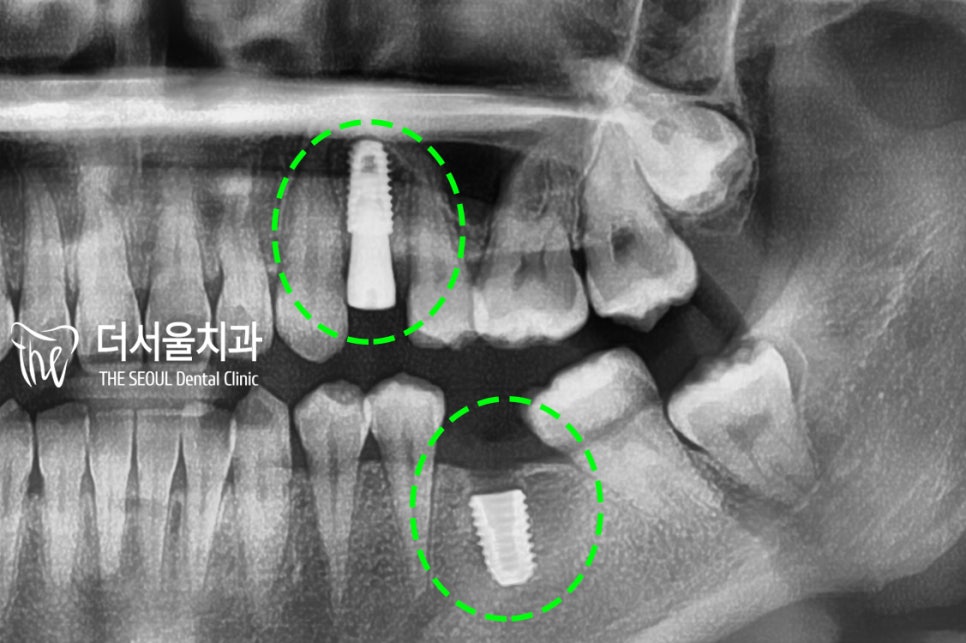

치과 치료에 대한 트라우마가 있으셨기에

발치 즉시 식립을 계획했습니다.

먼저 컴퓨터 분석을 통해

식립 방향 및 위치를 확인한 후,

바로 픽스처를 심어드렸습니다.

잇몸 형성을 도울

치유지대주 (healing abutment)까지

체결을 한 뒤에

골융합, 잇몸 회복을 확인하고

최종 보철을 올려드리기로 했습니다.